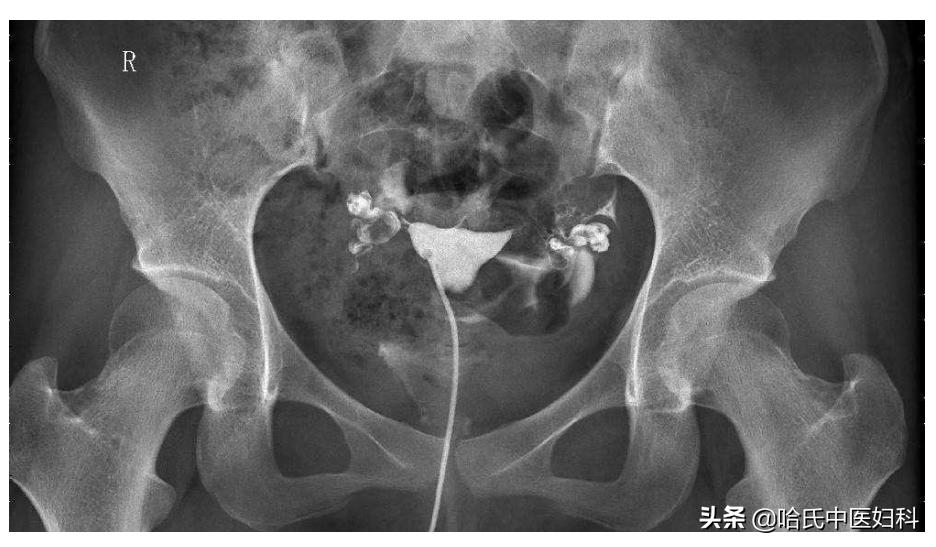

如今24岁的她已结婚嫁人,她老公也很疼她,可是结婚一年都没有孩子,老公检查没有问题,做了子宫输卵管碘油造影,结果提示双侧输卵管伞端堵塞。这下慌了,原本以为自己是易孕体质,如今被诊断为“继发性不孕”。

多次人流最容易导致就是输卵管堵塞,输卵管不通一般不明显, 少数输卵管不通患者,会出现小腹一侧的疼痛、或小腹两侧疼痛、下坠感、分泌物增多、腰痛等表现,或月经来潮时血量增多等 ,只有通过做输卵管通液实验后才得知。

在这里要特别说明, 备孕女性,一般在做输卵管造影检查之前,女性卵巢功能以及监测排卵,男方进行精液常规分析。如果以上都没有问题的话,此时建议患者行输卵管造影检查。